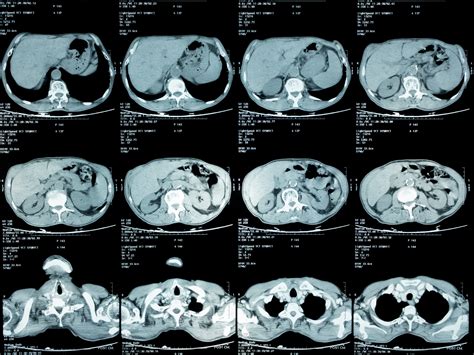

When your physician suspects an issue within your internal organs, they may recommend an MRI of abdomen to gain a clear, detailed picture of what is happening inside. Magnetic Resonance Imaging (MRI) is a sophisticated, non-invasive diagnostic tool that utilizes powerful magnets and radio waves to generate cross-sectional images of the structures in your abdominal area. Unlike X-rays or CT scans, an MRI does not use ionizing radiation, making it a preferred choice for many patients requiring detailed soft-tissue assessment of organs like the liver, gallbladder, pancreas, spleen, and kidneys.

An MRI of abdomen is rarely the first test ordered; instead, it is typically used to clarify findings from an ultrasound or CT scan or to provide a more detailed look at specific conditions. Doctors rely on this technology because it offers superior contrast resolution, allowing them to differentiate between healthy and diseased tissue with remarkable precision.

Once the MRI of abdomen is completed, the images are sent to a radiologist, a doctor specially trained to interpret diagnostic scans. The radiologist will analyze the images for signs of disease, inflammation, or structural irregularities. Because an MRI produces a vast number of images, it can take several days for a comprehensive report to be generated and forwarded to your primary care physician or specialist.